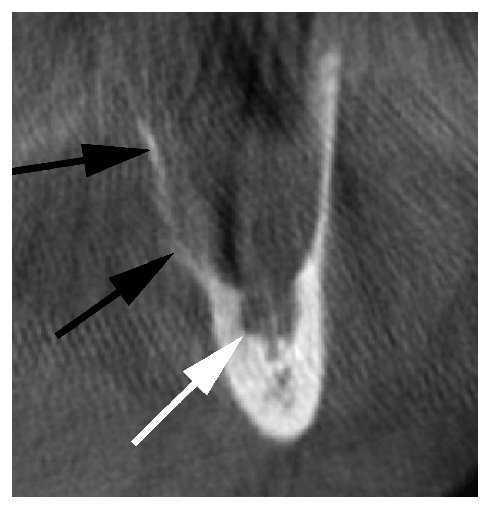

En la tomografía volumétrica digital dental solicitada de forma complementaria se aprecia una masa hipodensa circunscrita con un tamaño de 33 x 18 x 13 mm. El conducto dentario inferior izquierdo está desplazado hacia caudal y lingual (fig. 2). Se observa una apófisis alveolar tumefacta como consecuencia de la masa (fig. 3, flechas negras).

Figura 2. Tomografía volumétrica digital dental, plano sagital. Las flechas blancas marcan el trayecto del conducto dentario inferior (fig. 3).